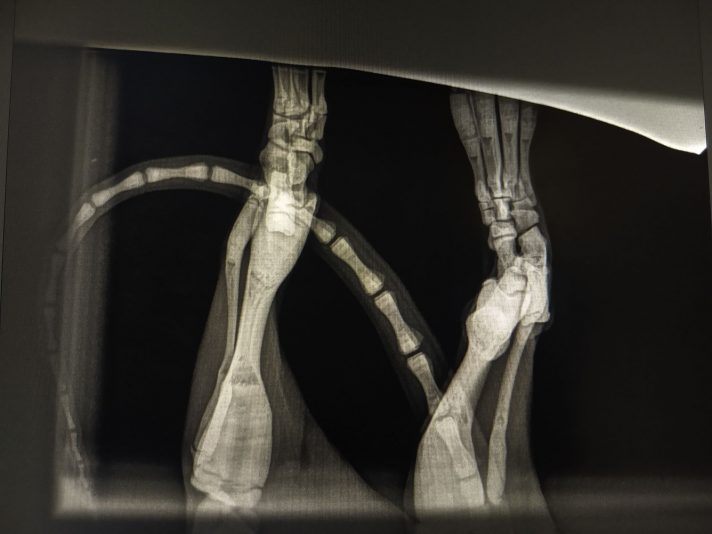

Vermoeden pituitary dwarfism - IGF1 normaal

Signalement: Kattin intact van 7m, Europese Korthaar

Anamnese: Enkele weken geleden reeds klachten van manken op achterpoot en gezwollen tarsus. Was de kleinste van het nest en groeide moeilijk. Sinds verhuis erg stil en zit veel minder leven in. Eten, drinken, urineren en defeceren nog normaal.

Klinisch onderzoek: rustig maar alert. HF…